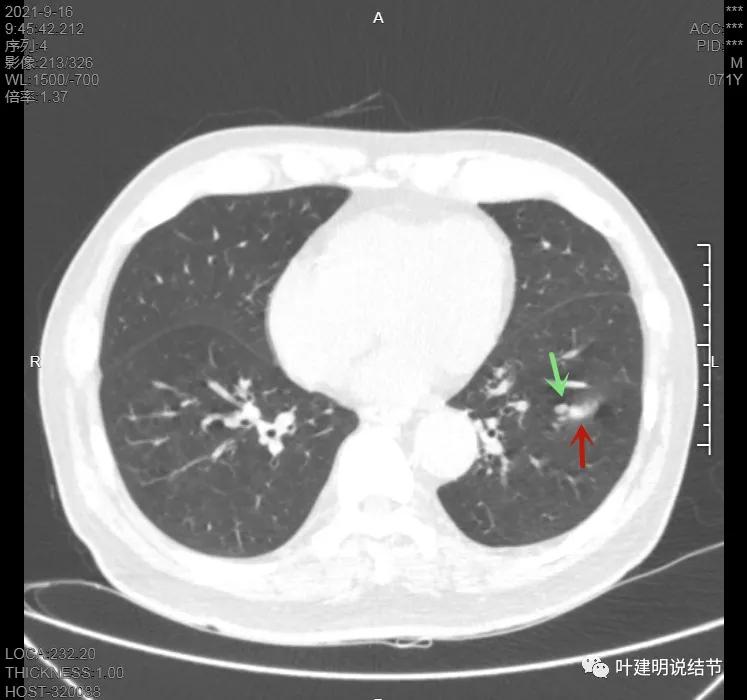

上图示病灶在左下叶,红色所指的与绿色箭头所指的是两个病灶,不相连的,实性结节

上图也示病灶是两个的,小的与大的之间有间隙的。大的病灶呈长方形似的

上图见主病灶长方形,边缘平直且光滑,没有毛刺、分叶或胸膜牵拉,粉色箭头示小病灶,在主病灶边上

上图示主病灶边缘非常光滑,膨胀性不明显

上图似乎边缘有点磨玻璃,但这可能是病灶横断面扫到策划相对较少或较薄的地方,其实并不是磨玻璃成分

上图是病灶下缘的样子